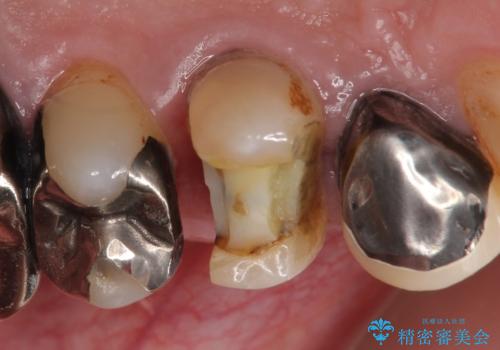

PGA(ゴールド)クラウン 脱離した銀歯の治療

- 古い銀歯が外れたので診て欲しいといらっしゃった方の症例です。

再根管治療後、PGA(ゴールド)クラウンによる補綴を行いました。

- PGA(ゴールド)クラウン…¥80,000、仮歯…¥10,000、ファイバーコア…¥20,000費用は治療当時の料金となります